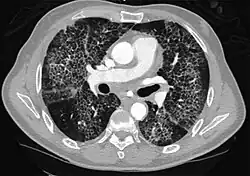

High-resolution CT image showing ground-glass opacities in the periphery of both lungs in a patient with COVID-19 (red arrows). The adjacent normal lung tissue with lower attenuation appears as darker areas.

CT image in patient with COVID-19 showing bilateral ground-glass opacities at the periphery of both lungs.

Ground-glass opacity is among the most common imaging findings in patients with confirmed COVID-19.[16][17] One systematic review found that among patients with COVID-19 and abnormal lung findings on CT, greater than 80% had GGOs, with greater than 50% having mixed GGOs and consolidation.[16] GGOs with mixed consolidation has most often been found in elderly populations.[18] Several studies have described a pattern among initial, intermediate, and hospital discharge imaging findings in the disease course of COVID-19. Most commonly, initial CT imaging reveals bilateral GGOs at the periphery of the lungs. During initial stages, this is most often found in the lower lobes, although involvement of the upper lobes and right middle lobe has also been reported early in the disease course.[16][18] This is in contrast to the two similar coronaviruses, SARS and MERS, which more commonly involve only one lung on initial imaging.[19][20] As the COVID-19 infection progresses, GGOs typically become more diffuse and often progress to consolidation.[11][18] This is sometimes accompanied by the development of a crazy paving pattern and interlobular septal thickening.[18] In many cases the most severe pulmonary CT abnormalities occurred within 2 weeks after symptoms began.[17] At this point, many individuals begin showing resolution of consolidation and GGOs as symptoms improve. However, some patients have worsening symptoms and imaging findings, with further increase in septal thickening, GGOs, and consolidation. These patients may develop lung "white-out" with progression to acute respiratory distress syndrome (ARDS) requiring treatment escalation.[17][21]